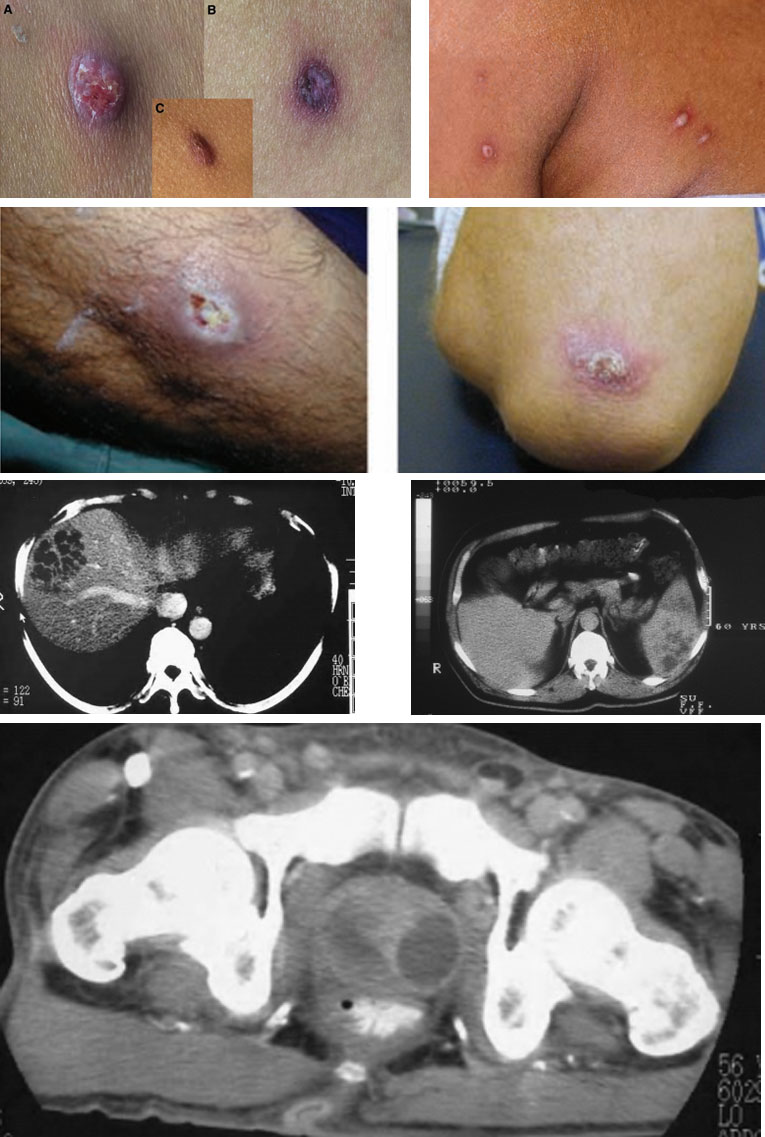

- Tổn thương trên da cơ xương, phần mềm: thường không phải triệu chứng đầu tiên

+ Vết loét hoặc mụn mủ đơn độc hoặc nốt, lâu liền: thể mạn tính, có thể là nguyên phát.

+ Mụn mủ có viền ban đỏ toàn thân: thể cấp tính, xuất hiện thứ phát sau NKH.

+ Abscess phần mềm dưới da, viêm mô tế bào.

+ Viêm khớp nhiễm khuẩn và viêm tuỷ xương: có tính chất mạn tính.

+ Xquang: thâm nhiễm lan toả hoặc tổn thương đông đặc rải rác 1 hay vài thuỳ phổi, thường gặp ở thuỳ trên, có thể kèm tràn dịch, tràn mủ màng phổi; hoặc tổn thương dạng hang áp xe